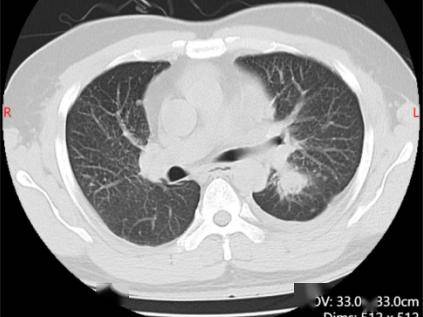

这一发现不仅为患者找到了全新的治疗方向,也填补了ALK罕见突变谱的空白。治疗团队经过充分的文献调研和多学科讨论后,决定给予患者ALK抑制剂阿来替尼靶向治疗。仅仅一个月后,复查胸部CT显示左肺上叶病灶较前明显缩小,疗效评估达到部分缓解(PR),患者的咳嗽、胸闷等症状完全消失,也摆脱了化疗带来的严重不良反应。

靶向治疗前左肺下叶肿块25mm

靶向治疗后左肺下叶肿块5mm